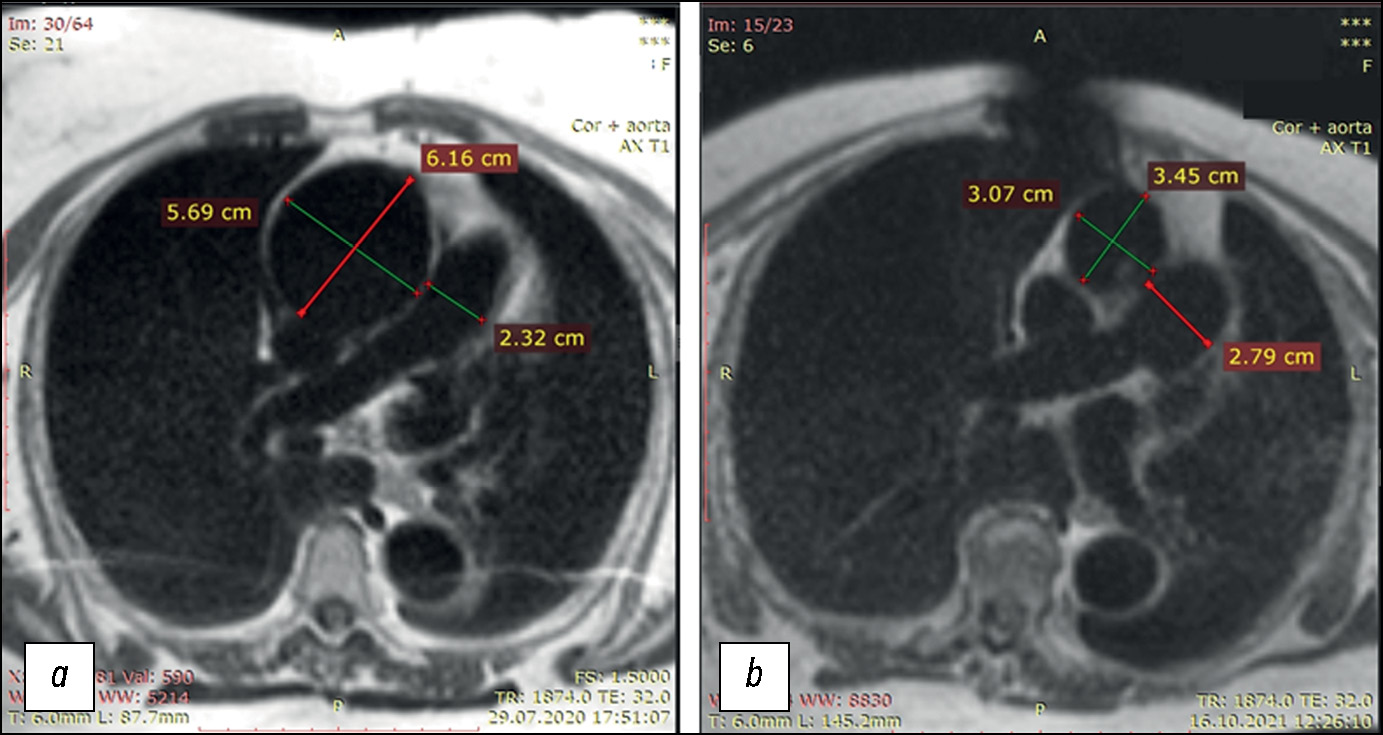

Slice thickness: 5–8 mm; matrix: 256 × 392 or 256 × 256. Axial T1WI chest MRI with respiration and ECG gating, with increased TR of 1,850–1,900 ms and TE of 32 ms, was performed as a component of cardiac and chest MRI with ECG gating (Fig. 1). This mode provides visualization of large thoracic vessels, including their walls. Owing to the borderline glomerular filtration rate (<30 mL/min × 1.73 m2), additional paramagnetic contrast enhancement was not used.

Fig.1. Transverse slices of T1-weighted images of the chest organs, including the thoracic aorta, at the pulmonary artery bifurcation level in patient B-k: (a) before prosthetic replacement of the thoracic aorta expanded due to aneurysm; critical ascending aortic aneurysm with a >6 cm lumen expansion; (b) after prosthetic replacement of the thoracic aorta expanded due to aneurysm; normal lumen of the ascending aorta. The descending aorta was normal before and after surgery. The pulmonary artery expanded to 27 mm after surgery, compared to 23 mm at admission. Postoperative tomography revealed an artifact in the chest area due to a wire fixator.